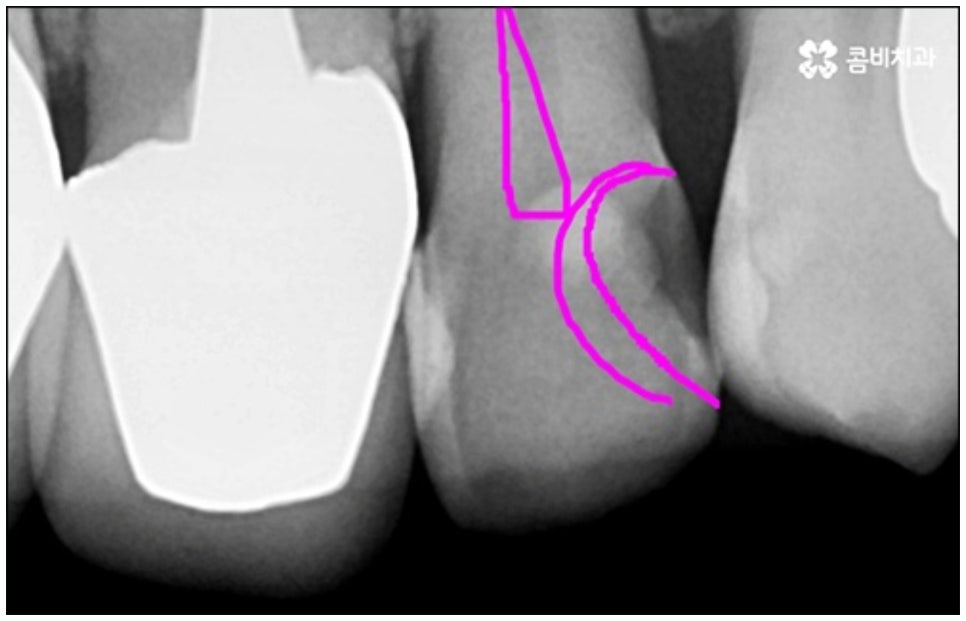

예를 들어서 오랜 치주염으로 퇴축이 진행되어 잇몸이 이미 많이 내려앉은 경우, 심한 치아 뿌리 염증으로 잇몸뼈가 상당부분 녹은 경우, 노화나 지병으로 인해 골밀도가 낮고 잇몸뼈가 약해져 지지가 어렵거나 쉽게 부서지는 등 뼈의 상태가 양호하지 못한 경우 등에 있어서는 발치 후 즉시 임플란트를 식립하는 방식이 적합하지 않으며 치아가 한꺼번에 여러개 손상된 경우에도 6~8주 정도의 시간을 두고 무리하지 않게 단계적으로 식립하는 것이 혹시 모를 부작용을 막고 장기적인 안정성을 높이는 방법이라고 할 수 있어요.

이때 당일임플란트 시술은 정밀함을 요하는 고난도 치료에 속하는 만큼 의료진의 숙련도에 영향을 많이 받기 때문에 안정적으로 골이식재가 자리잡고 식립된 임플란트가 보다 오랜 기간 강한 저작력을 견딜 수 있도록 지속력을 높이기 위해서는 다양한 환자분들의 임상 치료 경험과 뛰어난 노하우, 정확한 판단력 및 세심한 실력을 갖춘 의료진에게 시술을 받으실 필요가 있습니다.

또한 한 번 식립된 인공 치근이 뼈조직과 골융합되고 난 다음에는 그 위치와 방향을 수정하기 어려운 만큼 혹시 모를 부작용이나 재수술 위험 없이 임플란트 치아를 사용할 수 있도록 안정성이 검증된 정품 재료를 사용하고 있는지, 잇몸 상태와 구강 구조를 세밀하게 체크할 수 있는 3D CT와 같은 정밀 검진 장비를 활용하는지 등등을 함께 꼼꼼하게 체크해 볼 필요가 있어요. 그리고 언급했던 것처럼 사후 관리 역시 임플란트 수명에 큰 영향을 주니 철저한 케어 시스템을 갖추고 임플란트 유지 관리를 도와주는 치과에서 진행하는 것 역시 중요하다고 할 수 있습니다.